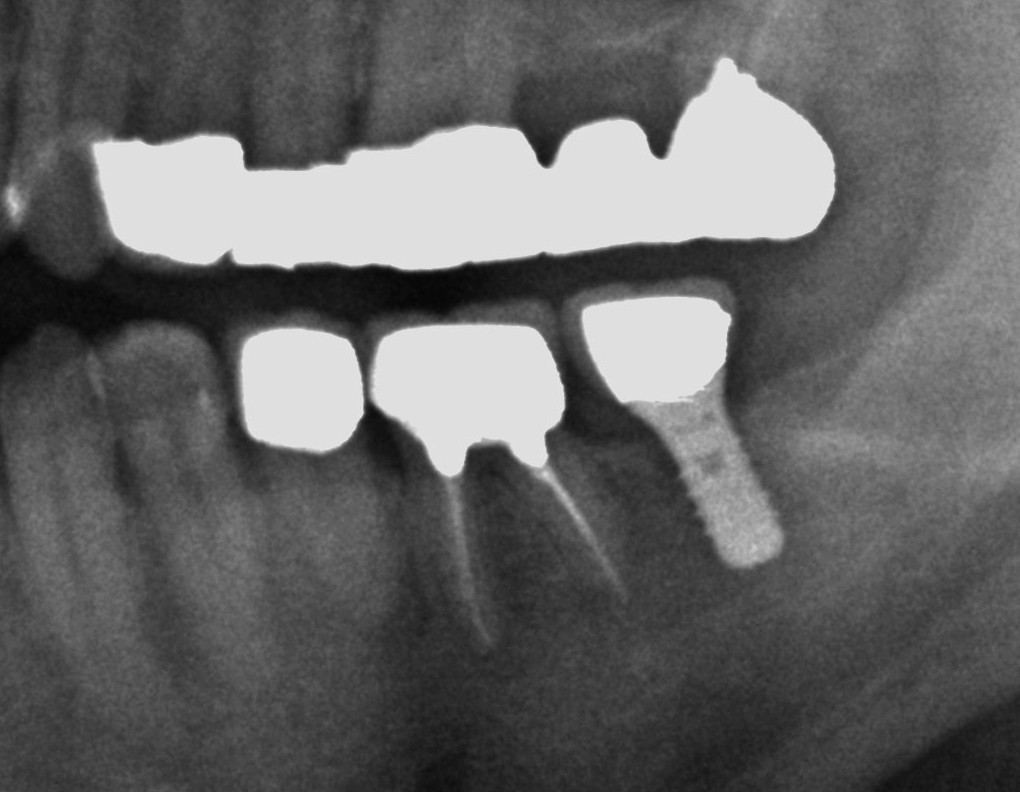

インプラントの形態には、左←のブレードタイプと呼ばれる板状のものと、右→のルートフォームと呼ばれる歯根の形のタイプがあります。(ルート=歯根)

ブレードタイプのインプラントは現在はもう使われていないと思います。

私もブレードタイプインプラントのメンテナンスや撤去を行った経験はありますが、埋入したことはありません。

現在は、ルートフォームが主流になっています。

ルートフォームタイプ(歯根の形)は当初はシリンダータイプと呼ばれる平らな表面でしたが、ネジ型の方が埋入時の安定性に有利とされていて、現在のインプラントはネジ山型の形態になっているものが多いです。